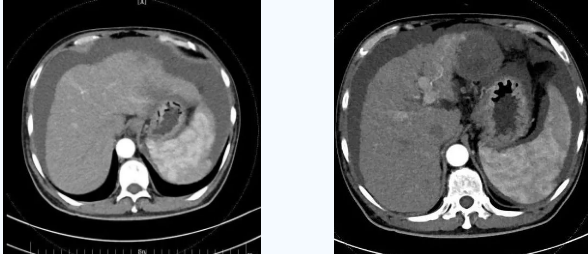

55歲的秦先生,于2021年10月被確診為肝癌晚期、慢性腎功能不全尿毒癥期,一直在口服靶向藥物進(jìn)行治療,規(guī)律行腎透析治療。直至今年4月因肝癌破裂出血行肝動(dòng)脈分支栓塞止血術(shù)后不久,秦先生開(kāi)始出現(xiàn)了反復(fù)大量腹水,只能先暫停癌癥治療,解決腹水問(wèn)題??墒乔叵壬奶幈疾▽めt(yī),腹水仍然沒(méi)有得到有效控制,于是在家人的多方咨詢打聽(tīng)下,慕名來(lái)到西安國(guó)際醫(yī)學(xué)中心醫(yī)院。

入院后,消化內(nèi)科五病區(qū)韓國(guó)宏院長(zhǎng)帶領(lǐng)團(tuán)隊(duì)對(duì)患者做了深入的檢查,檢查后發(fā)現(xiàn)患者“肝硬化失代償期、頑固性腹水、原發(fā)性肝癌、慢性腎功能不全尿毒癥期、2型糖尿病、高血壓2級(jí)”等病癥,韓院長(zhǎng)在對(duì)患者的病情進(jìn)行反復(fù)評(píng)估分析后表示,首先要明確患者目前腎透析后,仍然是大量腹水、無(wú)尿,那么腹水是肝源性的還是腎源性的,遂請(qǐng)多學(xué)科會(huì)診,結(jié)合相關(guān)檢查后明確,秦先生目前的大量腹水是由于門脈高壓導(dǎo)致的頑固性腹水,只有先解決門脈高壓導(dǎo)致的頑固性腹水,才可以繼續(xù)進(jìn)行癌癥治療,于是,韓院長(zhǎng)決定為患者實(shí)施TIPS手術(shù)。

由于大量腹水、晚期肝癌加上尿毒癥等的綜合病癥,手術(shù)難度和危險(xiǎn)系數(shù)都比平常增加了幾倍,面對(duì)這樣的情況,術(shù)前韓國(guó)宏院長(zhǎng)帶著團(tuán)隊(duì)反復(fù)分析討論,全面評(píng)估,在患者的各項(xiàng)指標(biāo)達(dá)到手術(shù)標(biāo)準(zhǔn)后,對(duì)患者實(shí)施了經(jīng)頸靜脈肝內(nèi)門腔靜脈分流術(shù)(TIPS),手術(shù)取得成功,術(shù)后患者恢復(fù)良好。

術(shù)后一個(gè)月秦先生來(lái)院復(fù)查,腹水已明顯較前減少,精神和飲食較術(shù)前明顯好轉(zhuǎn)。